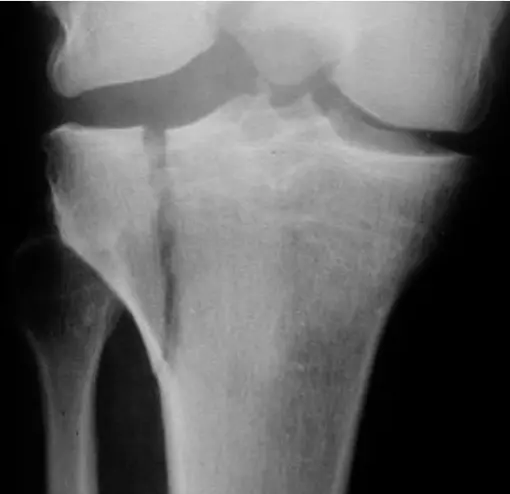

A 32âyearâold patient fell from a palm tree and now presents with pain and swelling around the left knee.

- Site: Lateral tibial plateau

- Fracture type: Comminuted

- Fracture line: Vertical split

- Displacement: Depressed

- Special issues: CT scan required for detailed assessment

- Management needed: Surgical intervention